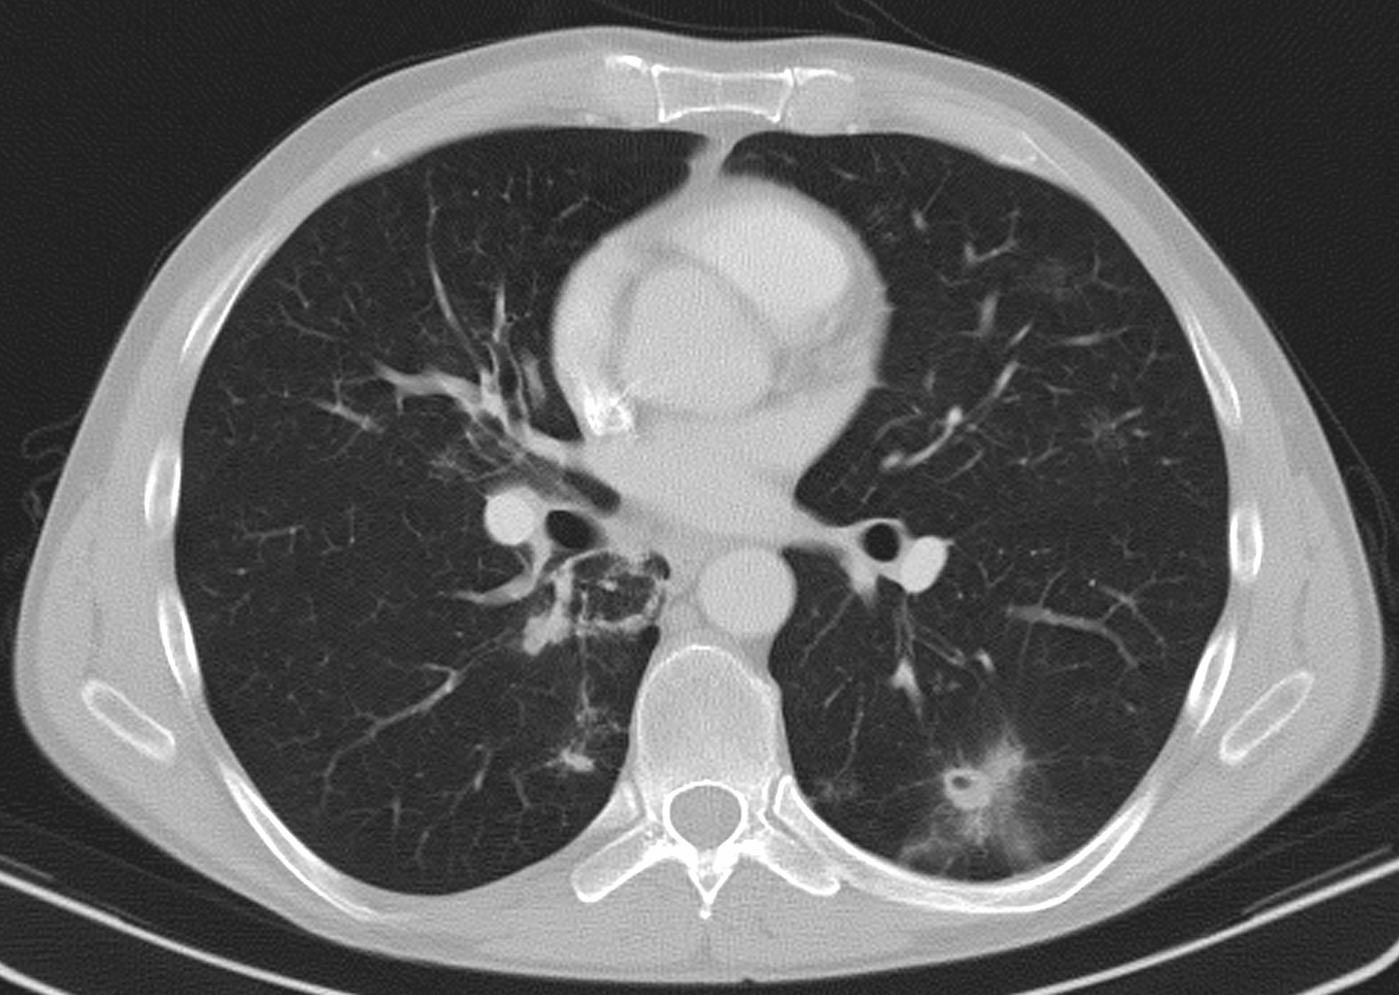

60 year old man, secondary pulmonary lesions due to kidney tumor, underwent target therapy.

Lobulated nodule in the left lung, associated with the pleura dorsobasally.

Lobectomy because of right lung adenocarcinoma, (brain metastasis). (by the contribution of Zsuzsanna Monostori, MD, PhD)